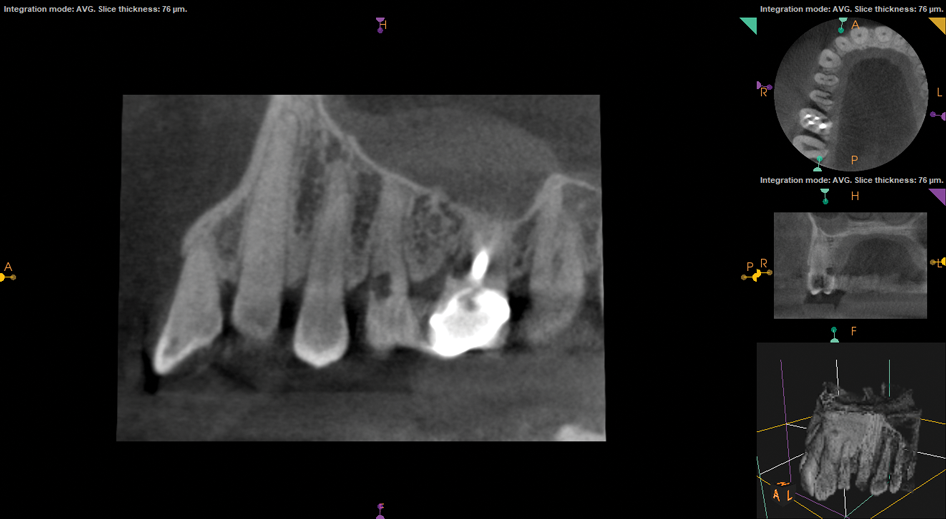

(1.) Preoperative CBCT scan showing Class 2 ECR defects on teeth Nos. 3 and 4 that were surgically accessible.

Figure 1

If an ECR lesion is inaccessible externally or internally, and it is neither symptomatic nor associated with pathologic bone loss, active monitoring represents a reasonable treatment alternative. This is frequently the treatment of choice for patients presenting with Heithersay Class 4 ECR defects or truly inaccessible Class 2 or Class 3 defects. Annual reevaluation is recommended for these patients, and the use of cone-beam computed tomography (CBCT) imaging should be considered.5,16

If an ECR lesion is surgically accessible, external repair with gingival flap surgery is the treatment of choice (Figure 1 through Figure 6). When considering external repair, clinicians should evaluate each case for potential postoperative esthetic concerns, such as the possibility of recession following surgical repair.6,7 Moreover, clinicians should assess the overall restorability of affected teeth because the surgical repair of large ECR lesions may predispose them to fracture.6 When a Heithersay Class 1 lesion is diagnosed, nonsurgical root canal therapy (NSRCT) in addition to the surgical repair is often unnecessary. However, in Heithersay Class 2 or larger defects where pulpal involvement is suspected or confirmed, NSRCT may be necessary in addition to surgical repair.6 If NSRCT is indicated in addition to surgical repair, it is recommended that it be completed prior to surgery to avoid exacerbating pulpal disease.